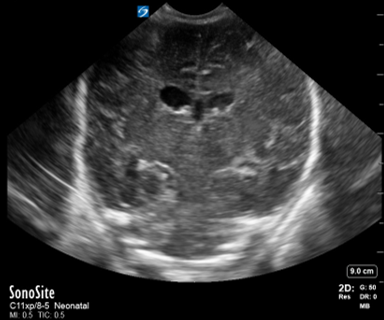

Neonatology Grade 1 IVH Pitfall 1 Image